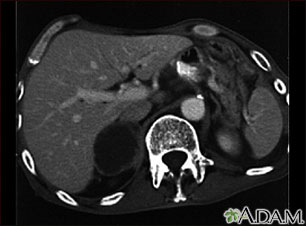

TC de la parte superior del abdomen que muestra una metástasis suprarrenal (diseminación del tumor a la glándula suprarrenal, encima del riñón) en una persona con cáncer de pulmón.